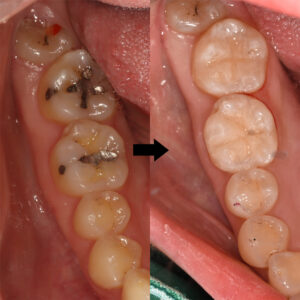

위 환자분은 구강에 오래된 아말감으로

구치부가 수복되어 있는 상태였는데요.

검진 차 내원하셨을 때 아말감 주변과

하방으로 이차 우식이 발생되어 있었고,

아말감이 부분적으로 탈락되어 있었어요.

충치치료를 위해 먼저 수복되어 있던 아말감을

제거하였으며, 다행히 부위가 깊고 넓지 않아

레진으로 치료를 진행할 수 있었어요.

치료 마무리 전, 후 사진이에요.🔍

인접하고 있는 자연치아들과 유사한 색상을 띄며

형태를 회복한 모습을 보실 수 있어요.